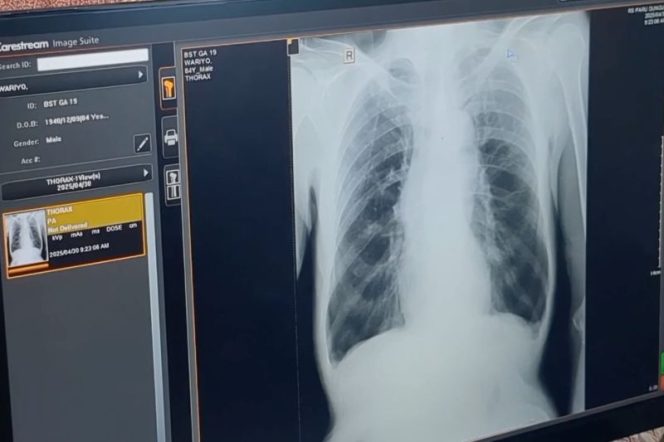

Foto: ANTARA News